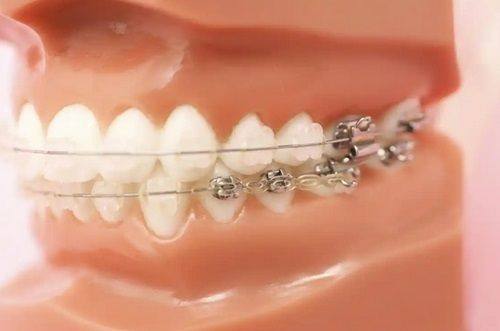

雷开英从事口腔临床工作20余年,曾在公立医院从事口腔临床工作10余年,在成人矫正、青少年矫正、儿童早期干预矫正及矫正修复联合调节等多个口腔诊疗领域拥有丰富经验,擅长美学修复及种植牙等项目。作为执业医师,她深耕口腔临床多年,技术扎实全面,所在的乐山雷开英口腔诊所位列乐山牙科医院排名前十,诊所注重患者舒适体验与治疗效果,项目价格合理,凭借专业的诊疗服务获得了当地大众的较高评价,在牙齿矫正、种植牙等领域的口碑都很不错。